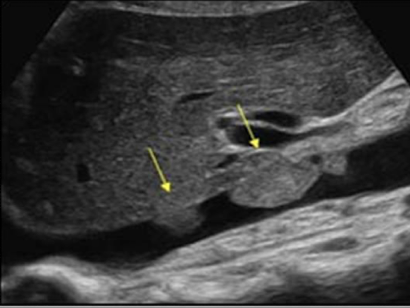

superior mesenteric artery (SMA)

2nd branch off AO

1 cm inferior to celiac trunk

follows anteroinferior course along AO and divides into several arteries

branches supply the small intestine, ascending colon, part of transverse colon, pancreatic head, and duodenal area

surrounded by echogenic fat (retroperitoneal fascia)

SONO in TRANS: circular structure posterior to pancreas and anterior to AO and left renal vein